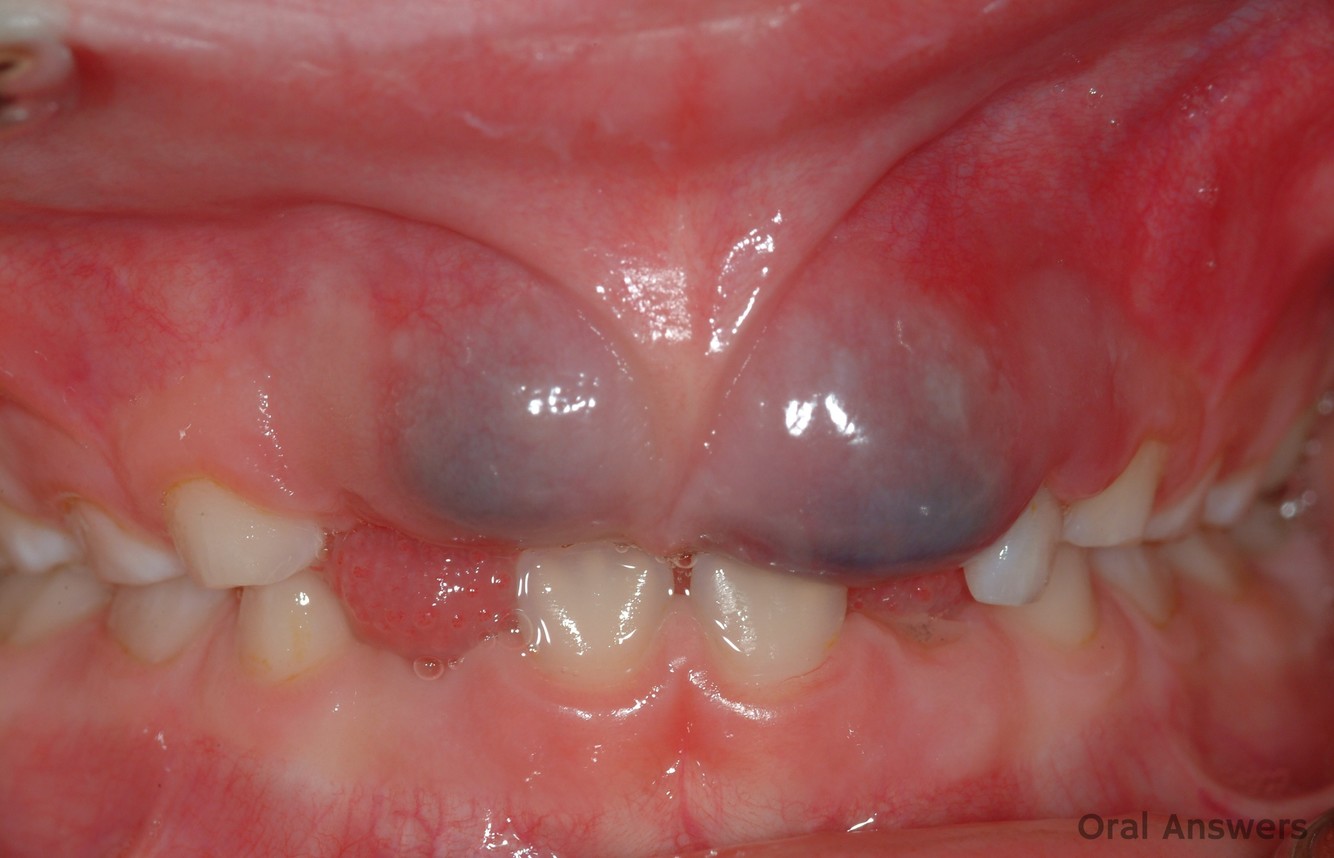

Eruption Cyst

SOFT TISSUE analogue of the dentigerous cyst

Tooth will errupt

Develops as result of separation of the dental follicle from around the crown o an erupting tooth

Clinically –> blue swelling

Radiographically –> tooth is erupting

Younger children

Looked radiographically for an errupting tooth